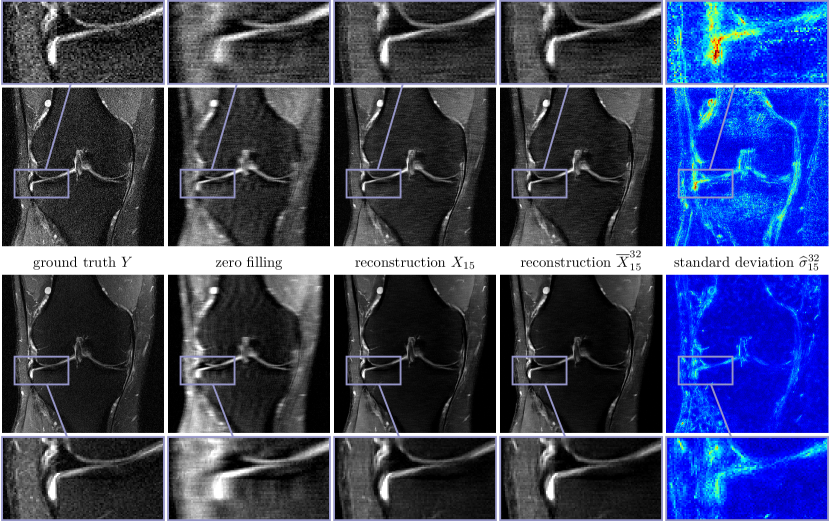

Likewise, Figure 5 depicts the corresponding results for PD-FS data and R=4𝑅4R=4 using the same entropy levels as before, all other parameters are the same as in the previous Figure 3. We remark that the signal-to-noise ratio is smaller in PD-FS data than in PD data and thus the reconstructions have a tendency to include more noise and imperfections. The inferior quality compared to PD is also reflected in the higher average intensities of the standard deviations.

Figure 6 shows the multi-coil reconstruction results for 888-fold undersampling and both data sets in the same arrangement as before, the entropy level is H¯(Σ)=31.41¯𝐻Σ31.41\overline{H}(\Sigma)=-31.41. As expected, the overall reconstruction quality is quantitatively and qualitatively inferior to the case R=4𝑅4R=4. As before, the difference of the deterministic and the stochastic restored images is relatively small and the standard deviations properly identify regions with higher uncertainties. Finally, Figure 7 depicts zooms of two different MRI reconstructions (R=4𝑅4R=4, PD), in each row the ground truth, two realizations, the stochastic reconstruction and the standard deviation are visualized. The regions highlighted by the arrows indicate structures and patterns that differ among various samples. The variability of the single realizations can be interpreted as hallucinations, which are properly detected in the corresponding standard deviations. This empirically validates that our proposed method to measure the standard deviation actually quantifies the magnitude of the model-related uncertainty. Figure 8 contains a visual comparison of our method with selected competitive methods from the fastMRI leader board. As a result, both E2EVN [42] and iRim [38] achieve slightly superior quantitative results at the expense of significantly more learnable parameters. In a qualitative comparison, we observe that our proposed method is capable of retrieving fine details, only the signal of a few high-frequency patterns is lost. Finally, U-Net [23] results are inferior to the considered competitive methods – both quantitatively and qualitatively.

Figure 5: Single (first row) and multi-coil (second row) MRI reconstruction results for PD-FS data and R=4𝑅4R=4. From left to right: ground truth images Y𝑌Y, zero filling, deterministic reconstructions X15subscript𝑋15X_{15}, stochastic reconstructions X¯1532superscriptsubscript¯𝑋1532\overline{X}_{15}^{32} andstandard deviation σ^1532superscriptsubscript^𝜎1532\widehat{\sigma}_{15}^{32} (00 Refer to caption 0.0350.0350.035).

Figure 6: Multi-coil MRI reconstruction results for PD (first row) and PD-FS (second row) data and R=8𝑅8R=8. From left to right: ground truth images Y𝑌Y, zero filling, deterministic reconstructions X15subscript𝑋15X_{15}, stochastic reconstructions X¯1532superscriptsubscript¯𝑋1532\overline{X}_{15}^{32} and standard deviation σ^1532superscriptsubscript^𝜎1532\widehat{\sigma}_{15}^{32} (00 Refer to caption 0.020.020.02).